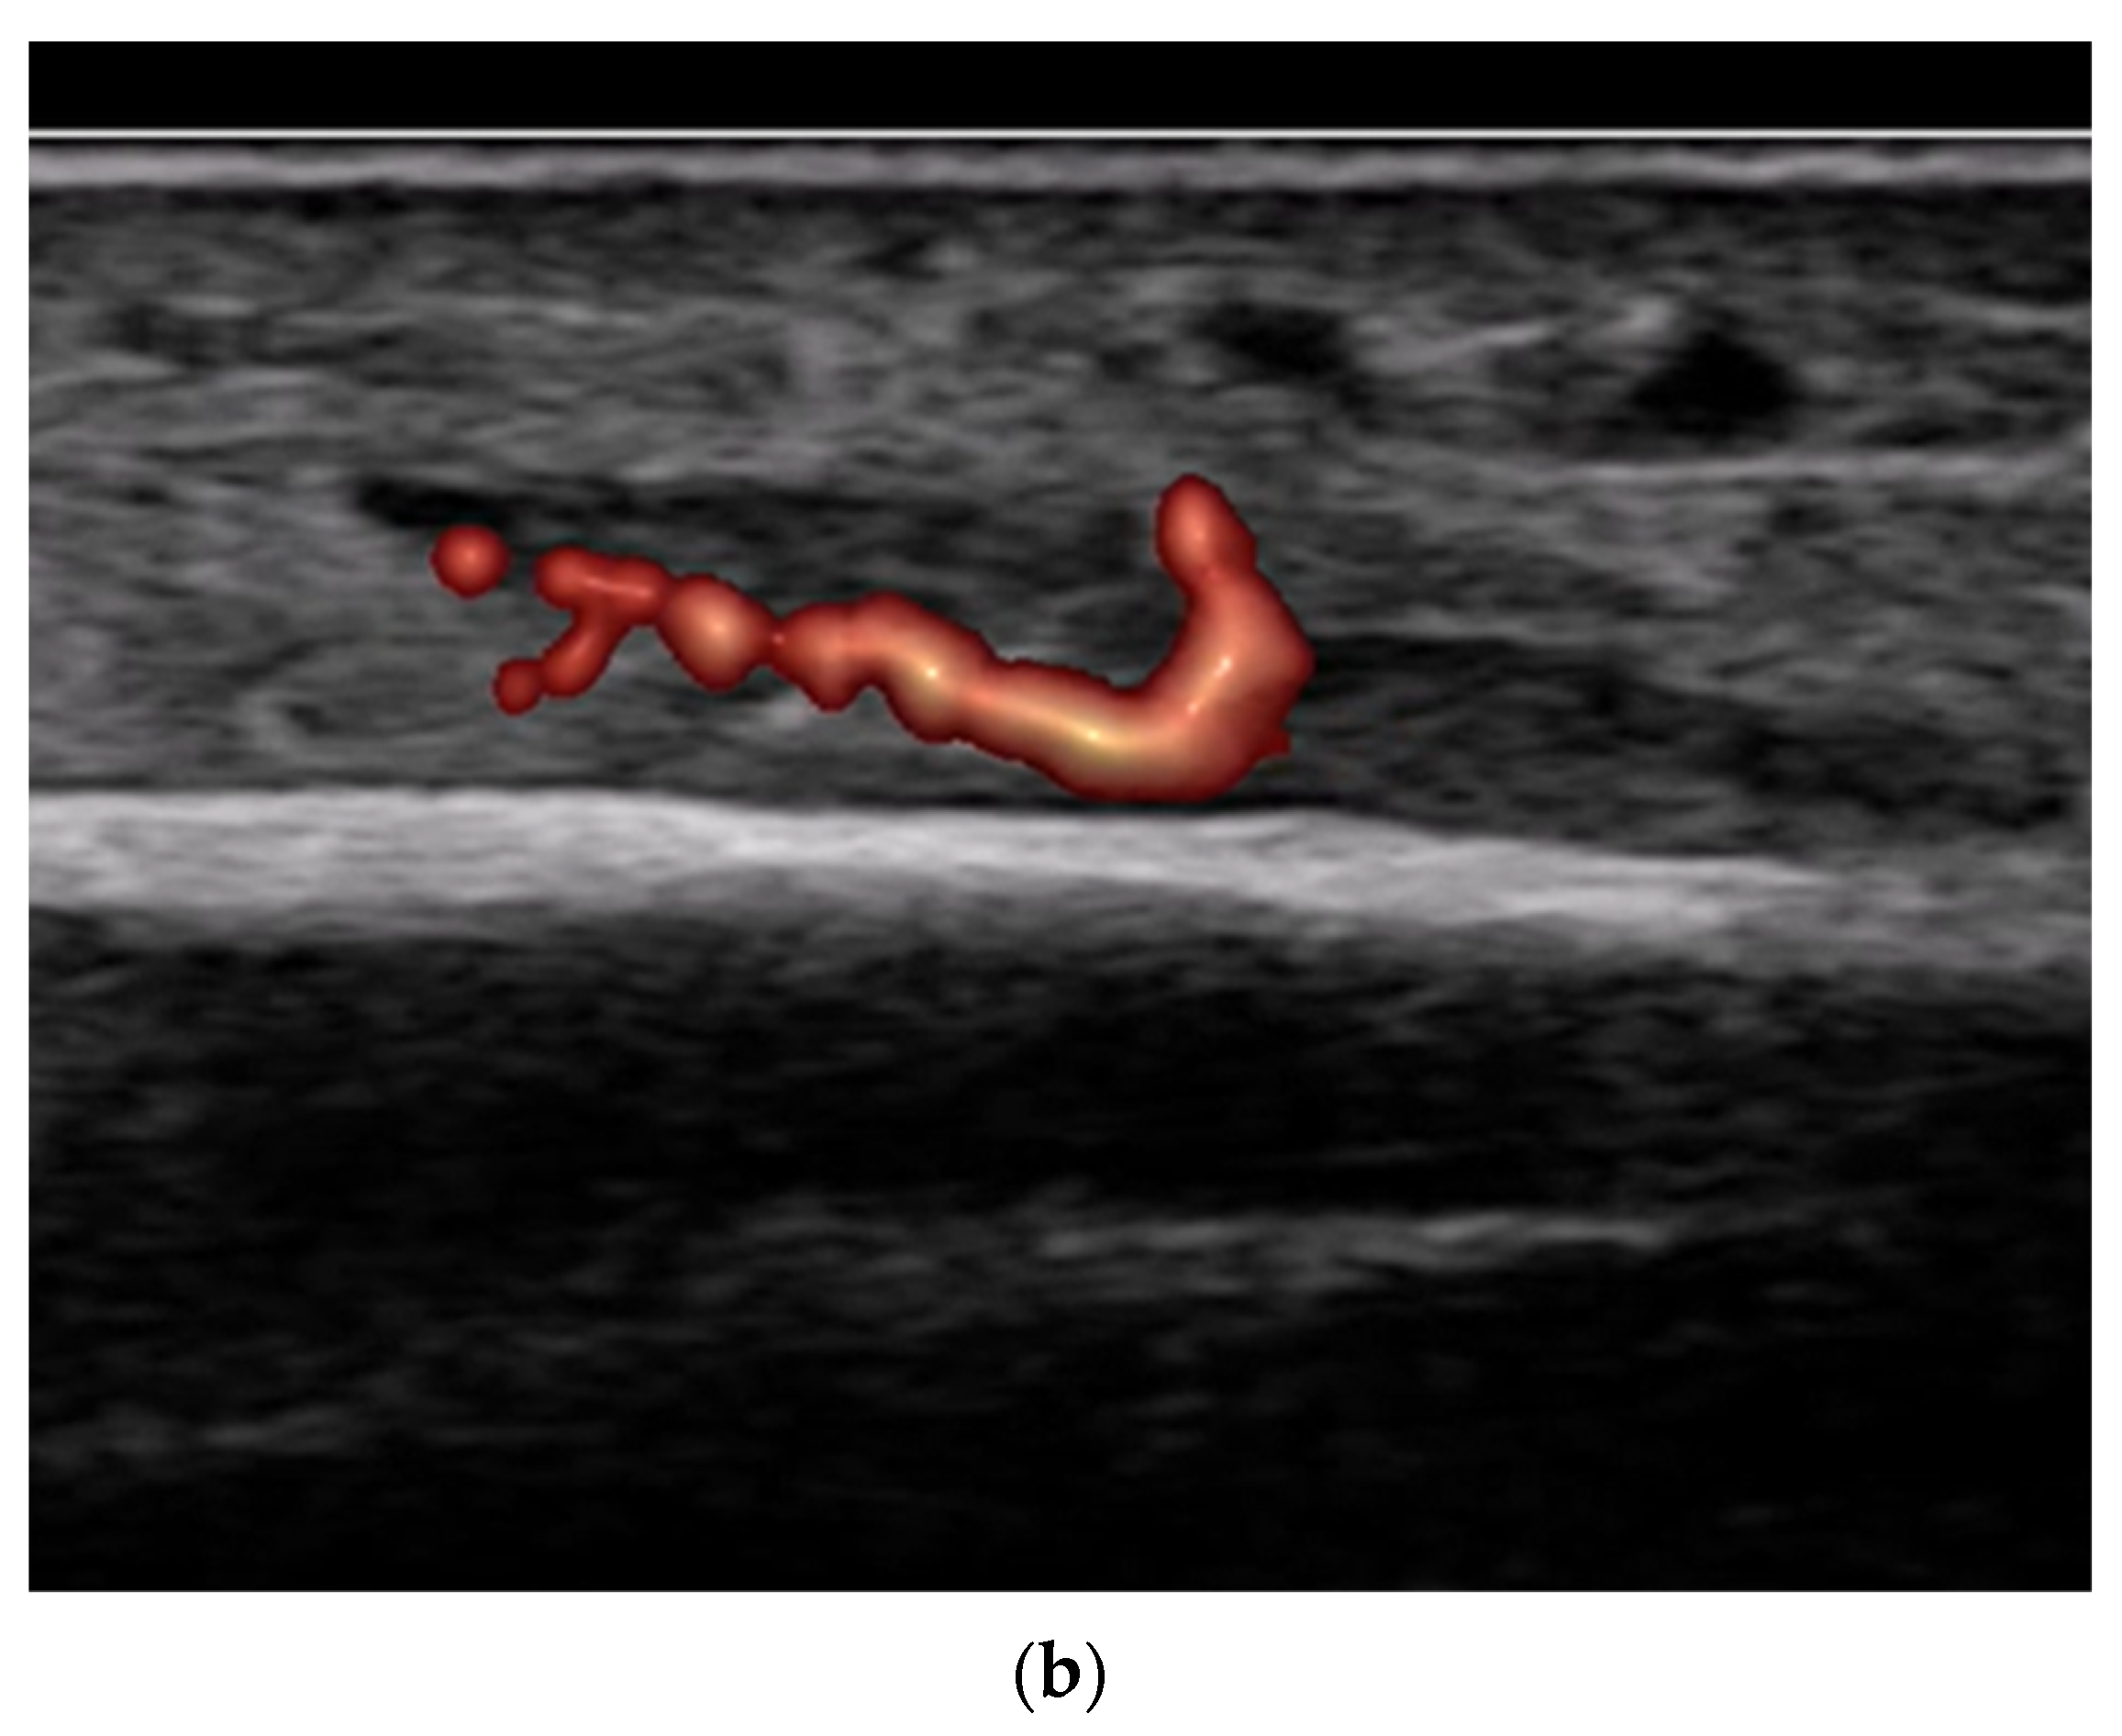

- Use of color and power Doppler: When employing Doppler techniques to assess vascularity related to inflammation or healing, care must be taken to avoid excessive probe pressure. Over compression of the tissue can collapse small vessels, leading to false-negative findings.

- Fracture healing monitoring: Ultrasound facilitates early callus formation. This can be useful for radiation-free monitoring of healing progression.